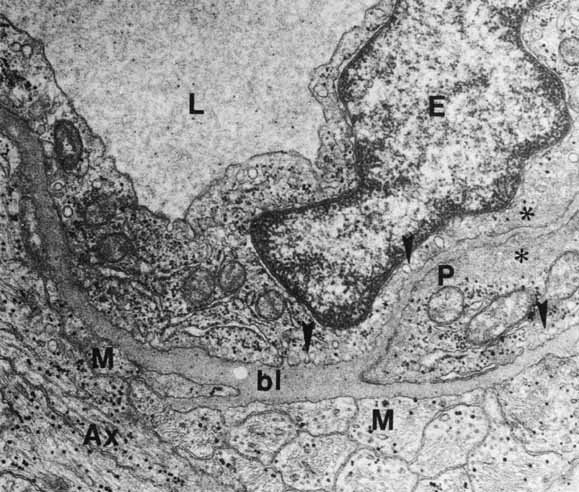

The ribbon or invaginating synapse, in contrast, is usually found in the presynaptic terminals of photoreceptors and bipolar cells in the retina (Fig. 20). They are also often observed throughout the invertebrate nervous system. The presynaptic terminal of the ribbon synapse is characterized by the presence of an electron-dense bar or a ribbon of approximately 1 um length that is oriented perpendicular to the presynaptic membrane. Reconstruction reveals that this ribbon is in fact a rectangular or horseshoe shaped plate composed of two osmiophilic electron-dense lamellae flanking an electron-dense central layer69,70 This synaptic ribbon is surrounded by a precisely arranged array of synaptic vesicles and appears to be anchored to the presynaptic membrane by three to five delicate electron-dense filaments. The shape and size of the synaptic ribbons can change depending on the maturation stage, activity state of the synapse, or light/dark cycle. Although the precise function of the synaptic ribbon is unknown, it has been hypothesized to function as a “conveyor belt” to channel synaptic vesicles to the presynaptic membrane for neurotransmitter release, to immobilize the vesicles in inactive synapses, storage device for synaptic transmitter, and to act as a diffusion barrier for presynaptic ions.69 In the inner plexiform layer, this synapse has two postsynaptic processes, forming a “dyad.” In the outer plexiform layer, there are three postsynaptic processes, forming a “triad” (see Fig. 20).

Fig. 20 Two ribbon synapses in a rod spherule (S) are surrounded by synaptic vesicles: (1) central bipolar dendrite terminal and (2) terminal buds of horizontal cells. Arrowhead points to arciform density (original magnification ×24,000).